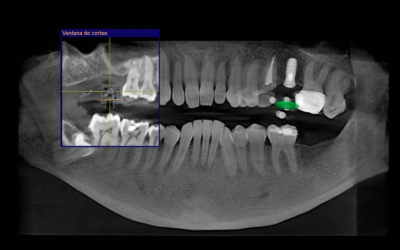

Radiología 3D: La tecnología al servicio de la planificación

La implantología se ha convertido en un tratamiento habitual en las consultas dentales. Los procesos han ido evolucionando y hoy en día encontramos técnicas como la Radiología digital 3D. Un estudio radiológico en 3D nos permite estudiar con gran precisión...